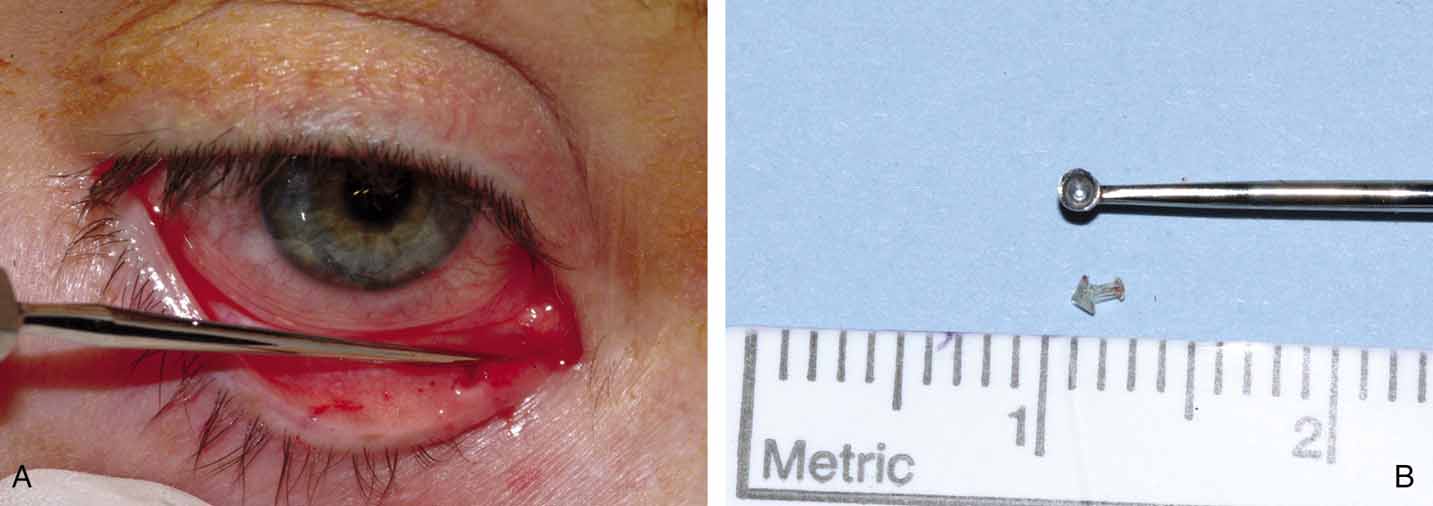

with bicanalicular stents, they should be watched for cheesewiring, or the slitting of the canaliculi and puncta (Fig. 32). This condition can occur if the loop is tied too tightly and is

also because of the rapid growth of young children. The loop has a fixed

length, so slitting of the canaliculi may occur as the face enlarges. A

slit of up to one half of the canalicular length does not seem to

cause any problems in the otherwise normal canaliculus, but nevertheless, it

is a complication that should be avoided if possible. The loop

should be tied loosely enough to allow for some growth, but not too

loosely such that the cornea could be irritated on adduction of the globe. Another

complication of Silastic intubation is the formation of a

granuloma of the punctum or canaliculus (Fig. 33). This problem can be corrected by simple excision of the granuloma

and cautery of the base.  Fig. 32 Cheesewiring of the lower canaliculus secondary to the tubing loop being